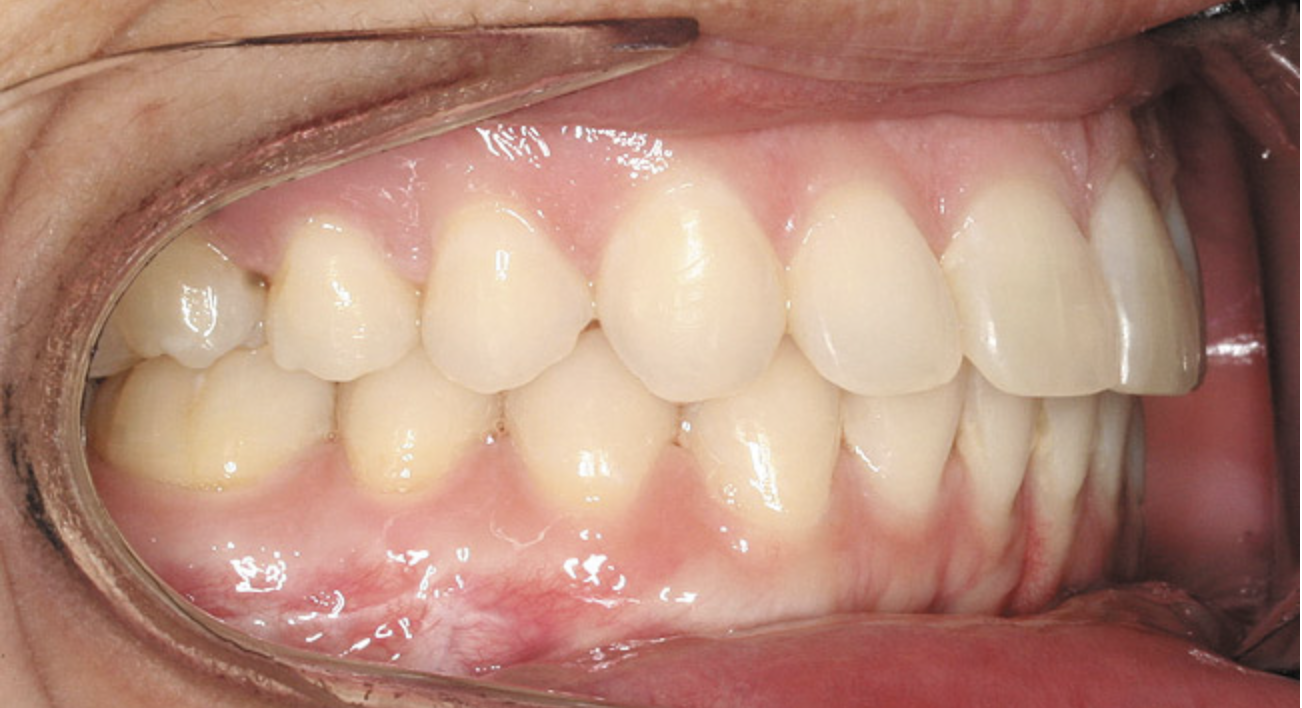

A stable TMJ is critical in establishing a normal functional occlusion. Unless the condyles are in a stable musculoskeletal position, there are always interferences to normal function and stress placed on the masticatory system.1-3,15 In orthodontics, the Angle classification of malocclusion using handheld models has been the standard to evaluate the fit of the teeth. However, it is not possible to truly identify the occlusion/malocclusion using handheld models. Before the occlusion can be evaluated, the clinician must ascertain the joint position and condition (Figure 7 and Figure 8).1,16

Figure 8  Intraoral view of the occlusion of patient from Figure 7 after retreatment. The occlusion is adequate to finish with equilibration.

Figure 8